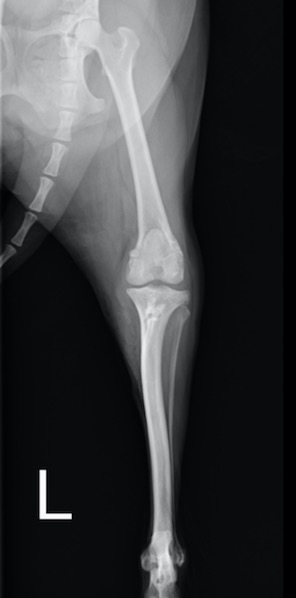

膝蓋骨が滑車溝の真ん中から左側(身体の内側)にずれているのが分かります

術後のX線画像です。膝蓋骨がきれいに滑車溝におさまるようになりました。